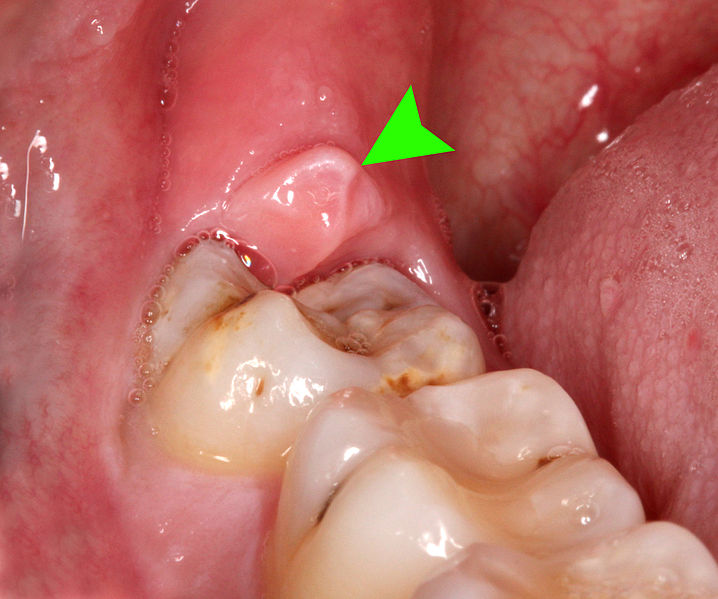

특히 사랑니가 부분적으로 분출되고 잇몸이 부분적으로만 덮일 때 칫솔질의 접근이 어려워 박테리아 플라크가 쌓여 충치의 위험이 증가하는 것이 일반적인데요.

맞은 편 이가 없거나 공동이 크고 나머지 어금니가 존재하는 경우, 일반적으로 추출이 권장됩니다.